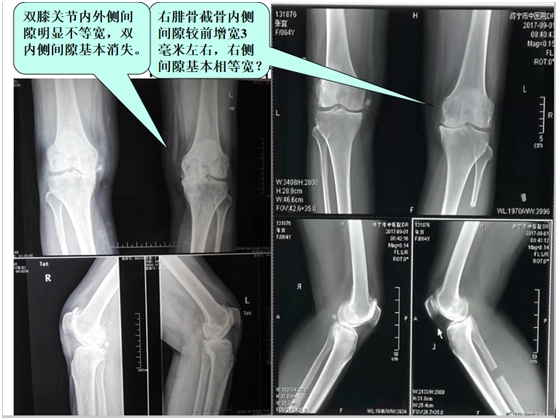

经科室讨论:在硬膜外麻醉下行左侧腓骨上段截骨(减压)均衡术+关节腔臭氧靶向介入术+激光清理术;7天后又在局麻下行双膝关节腔臭氧靶向介入+激光清理术。第一次微创手术后3天患者逐渐下床活动生活自理,出院时关节疼痛消失(见图片二  DR 片显示膝关节内侧间隙增宽);随访左侧膝关节活动范围逐渐恢复正常,可以赶集商店购物,做日常家务劳动兼照顾孙子辈上学。

图片二: DR 片膝关节退行性变内翻畸形,截骨前后关节间隙宽窄对比